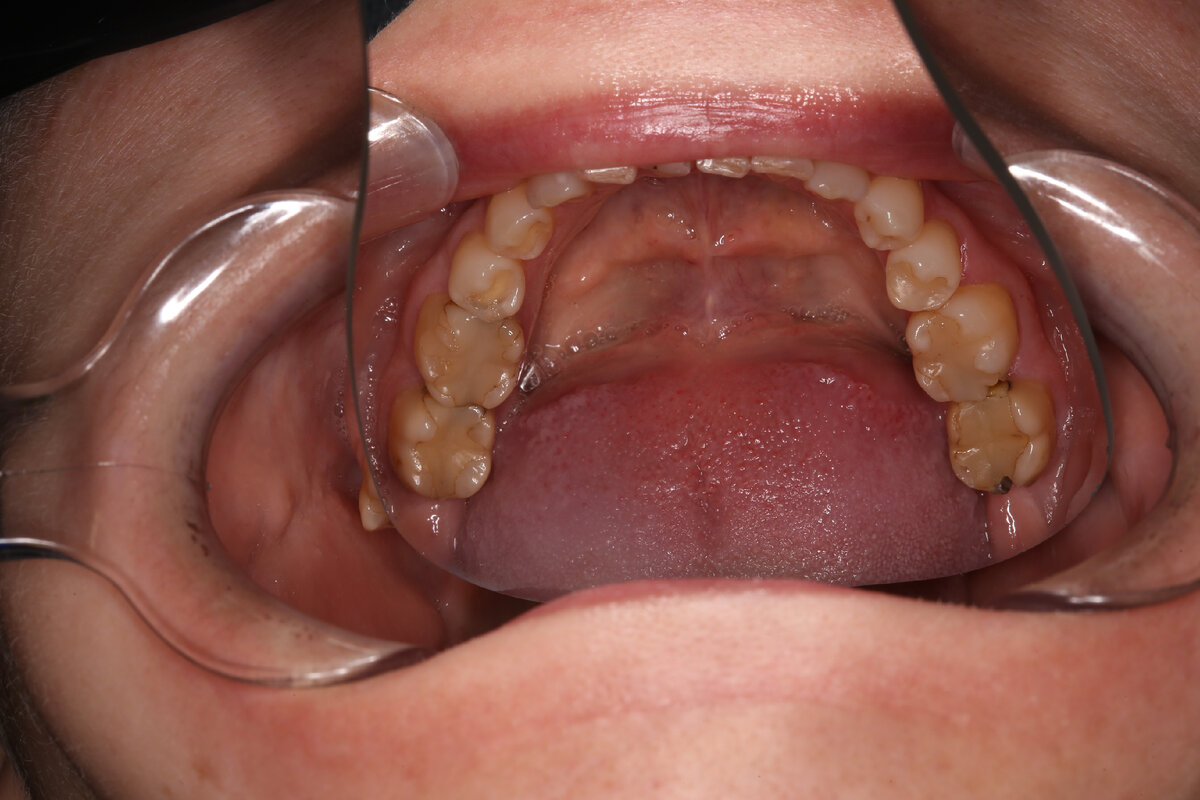

Представляем вашему вниманию работу нашего стоматолога-терапевта Аллахвердовой Софии. Комплексное терапевтическое лечение зубов (каждого зуба)

фото до лечения